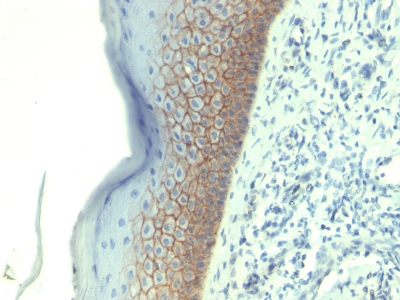

E-Cadherin/CD324, Monoclonal Antibody (Cat# AAA23896)

Does not react with Mouse and Rat. Others not known.